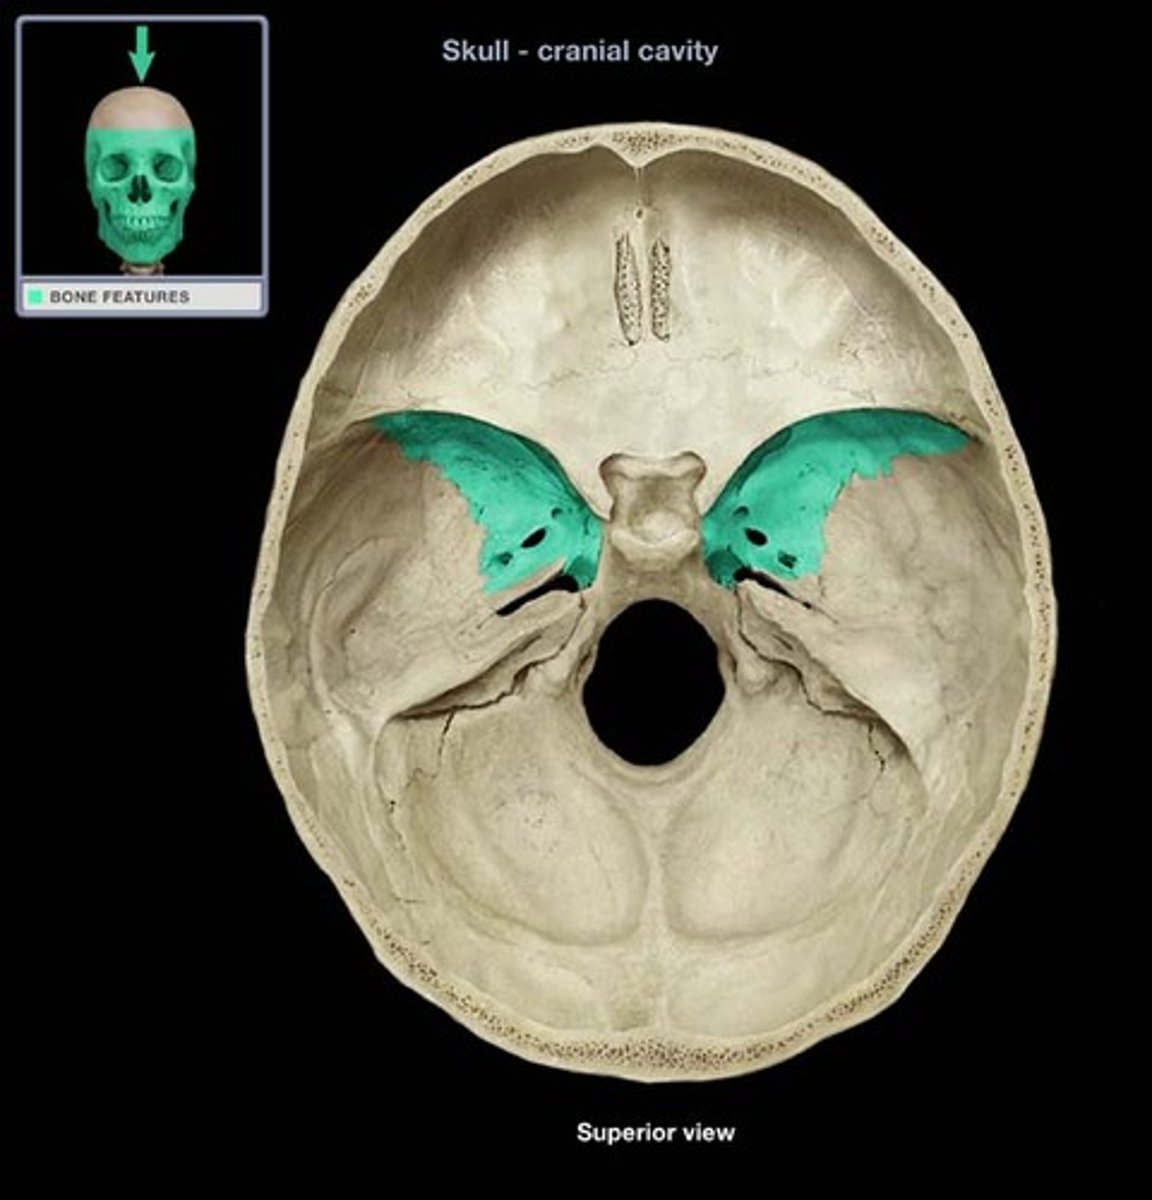

middle cranial fossa

sphenoid bone

lesser wings

greater wings

pterygoid processes

sella turcica

tuberculum sellae

dorsum sellae

posterior clinoid processes

optic foramen